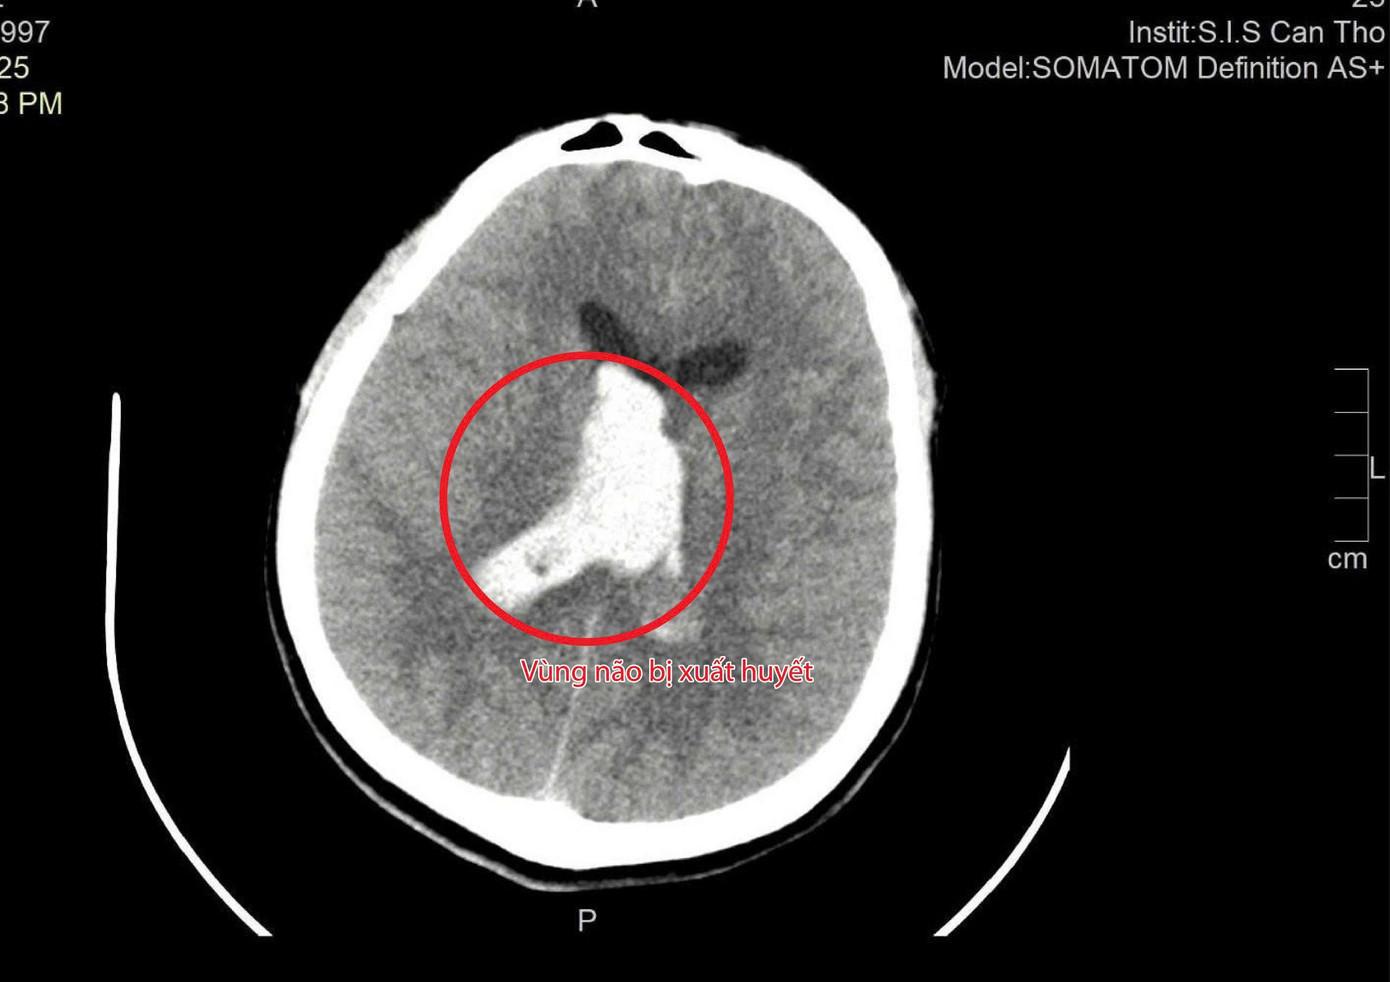

Trên hình ảnh kiểm tra, các bác sĩ ghi nhận vùng xuất huyết não gây tăng áp lực nội sọ khiến bệnh nhân nguy kịch

Chiều tối 12/11, thông tin về trường hợp bệnh nhân này, BS Tôn Nữ Thị Điểm, khoa Ngoại Tổng hợp Bệnh viện Đa khoa Quốc tế S.I.S Cần Thơ, cho biết: “Kết quả chụp CT cho thấy bệnh nhân T. bị xuất huyết trong não và não thất, kèm phù não nặng. Nếu không phẫu thuật ngay, áp lực nội sọ tăng nhanh sẽ đe dọa đến tính mạng”.